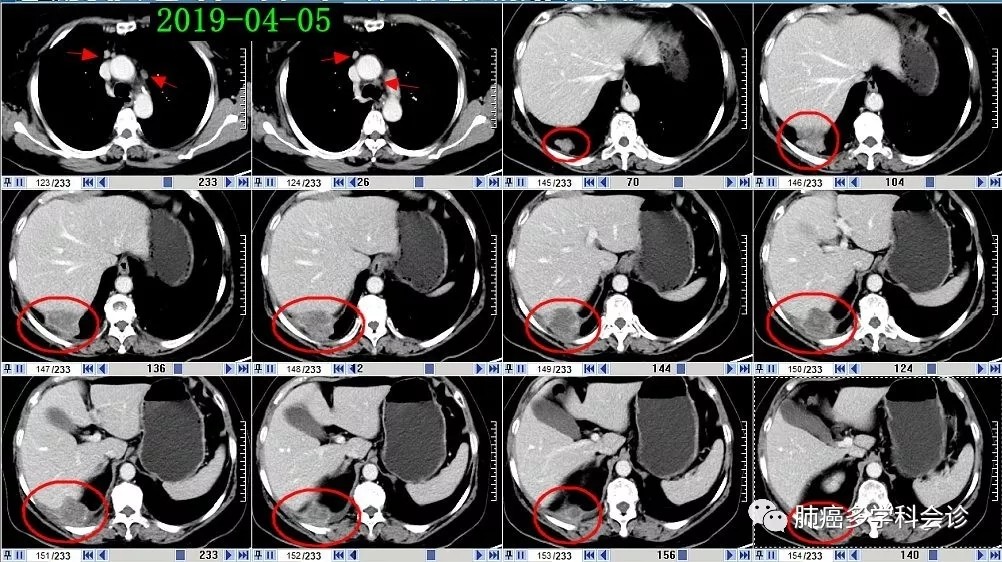

于术后20个月左右肿瘤复发,PET-CT(2019-03-23):右肺上叶支气管断端软组织影、代谢较活跃,考虑复发;膈肌右上份上方团块状软组织影代谢活跃,纵膈(2R区)及膈上前群肿大淋巴结代谢稍活跃,考虑转移。

2019-05-10复查CT,与2019-04-05 相比,肿瘤明显缩小: